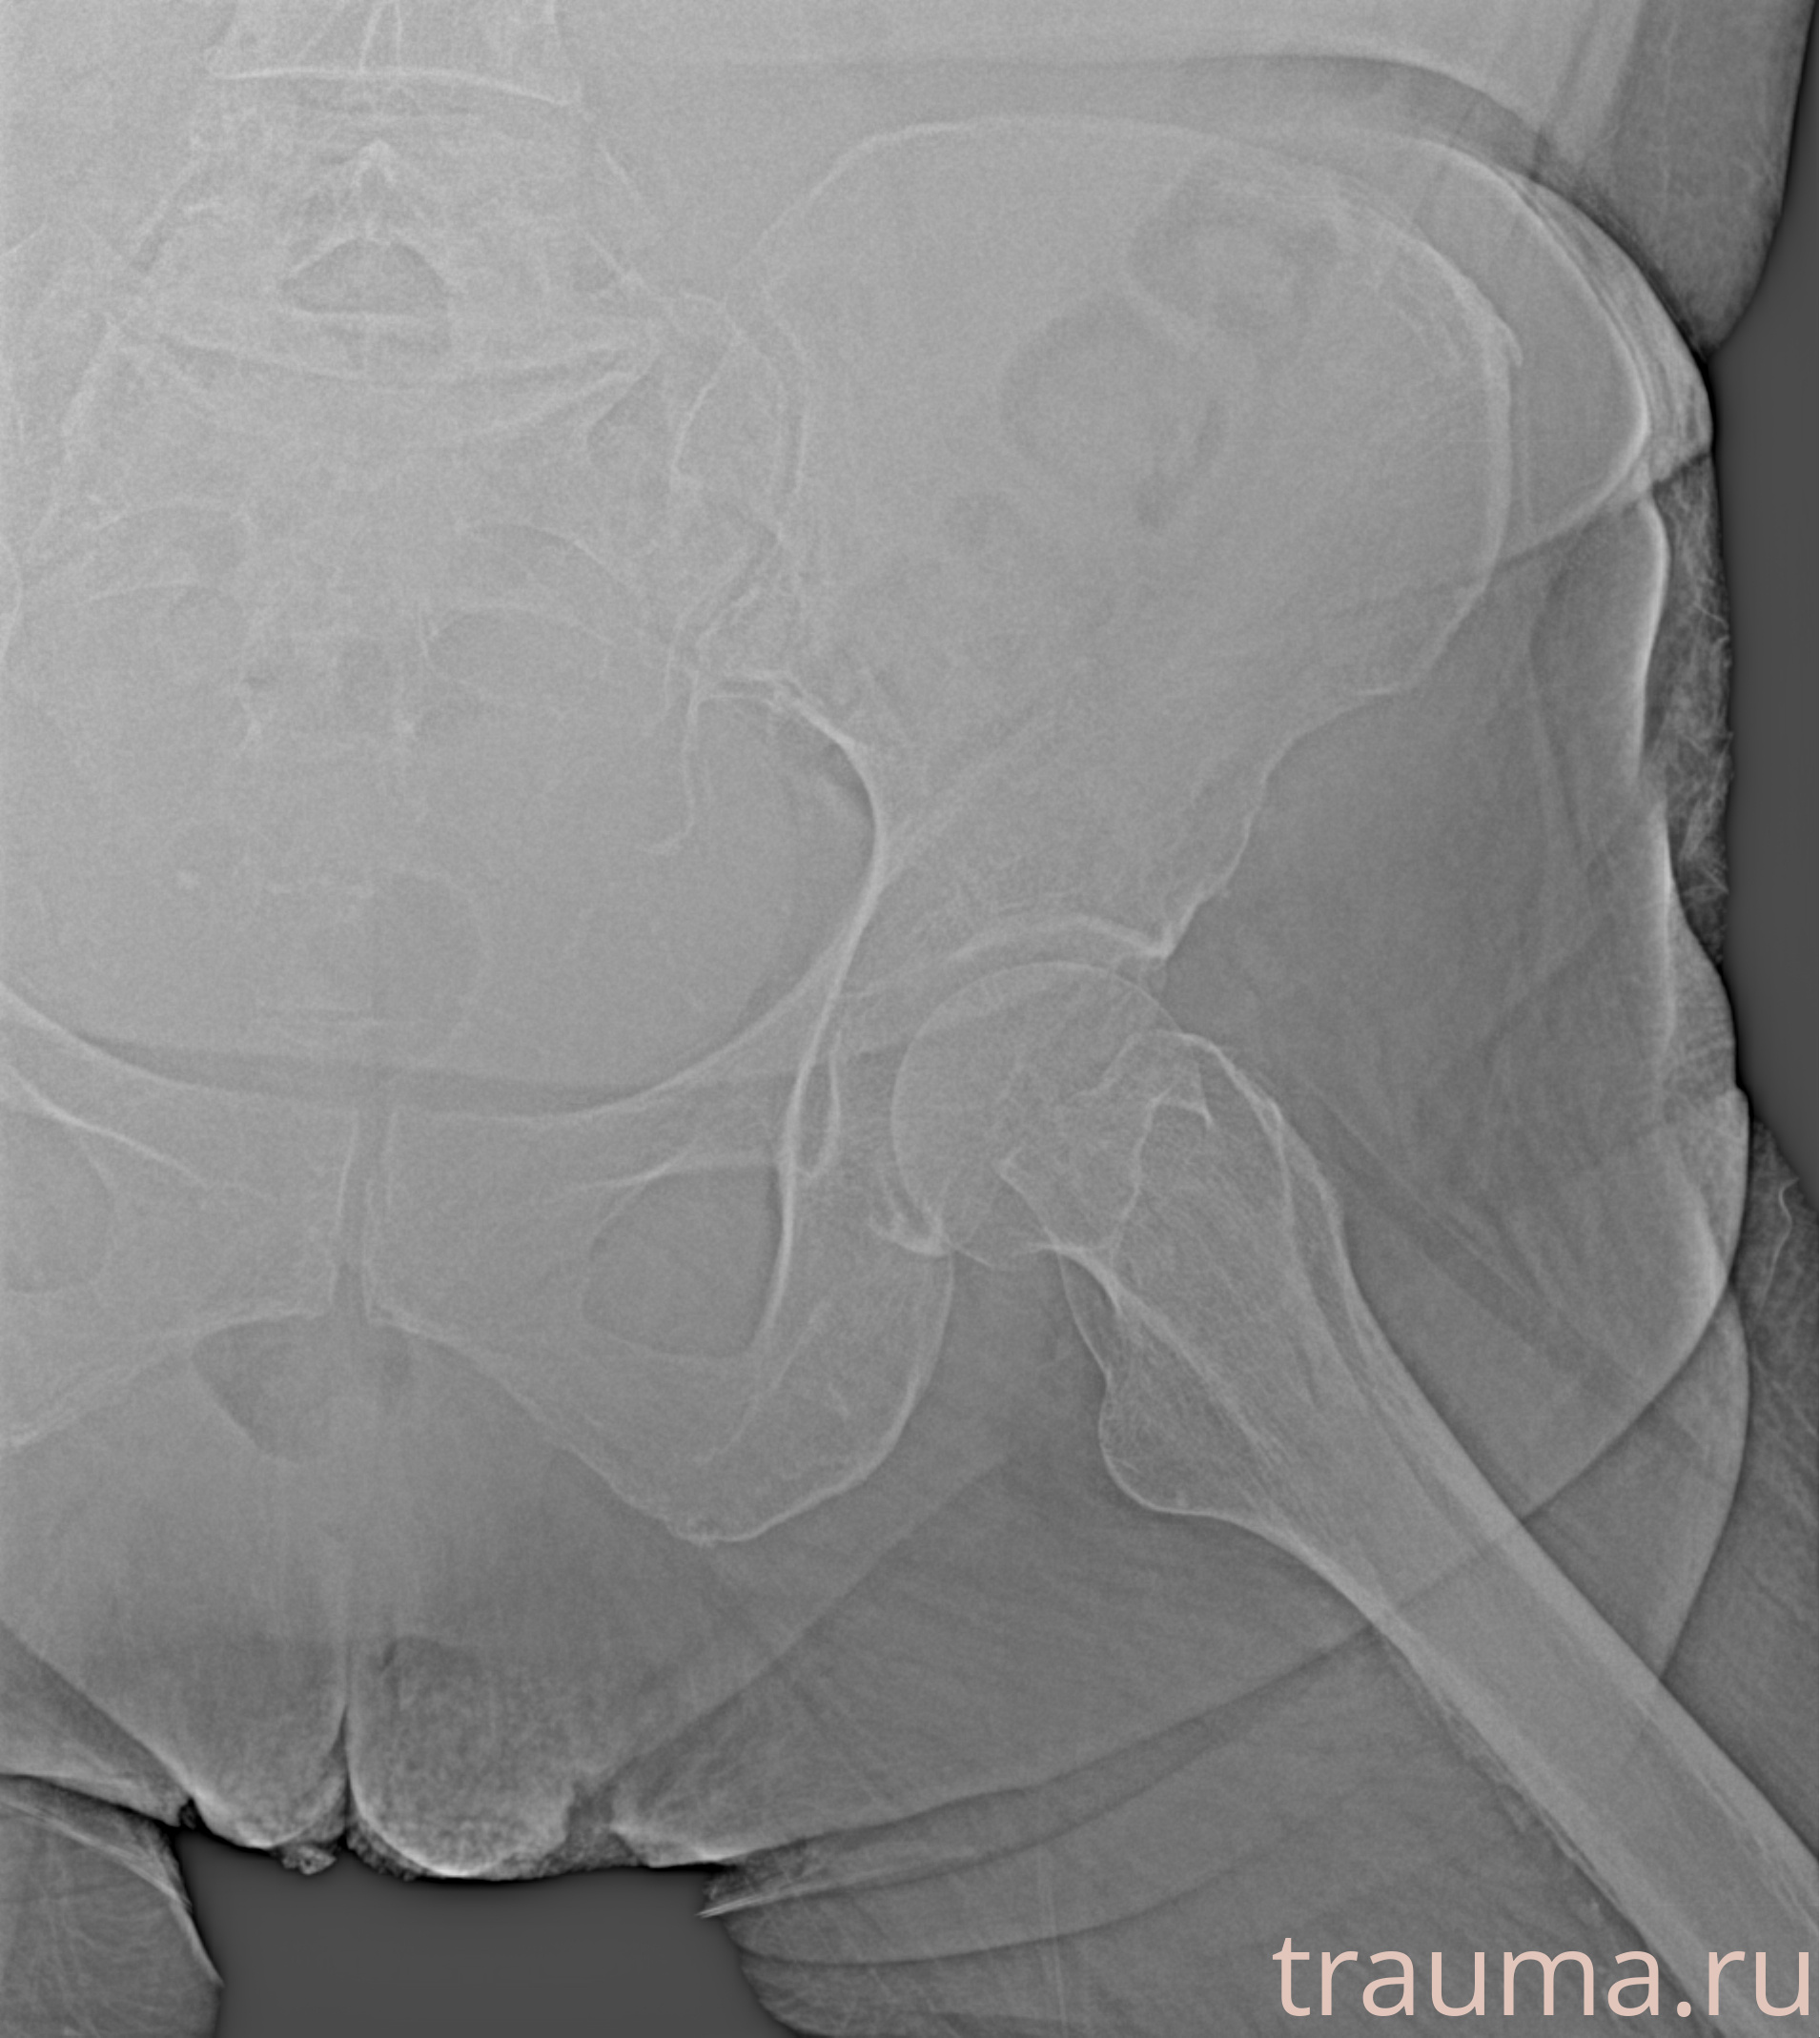

Рентгенограммы

Рентген на дому: по вашему адресу приезжает врач-рентгенолог, травматолог-ортопед с мобильным рентгеновским аппаратом, проводит диагностику травмы или заболевания, делает необходимые рентгенограммы, дает рекомендации по дальнейшему лечению. Получить качественные снимки в домашних условиях возможно благодаря уникальной методике, разработанной МосРентген Центром для института  Склифосовского